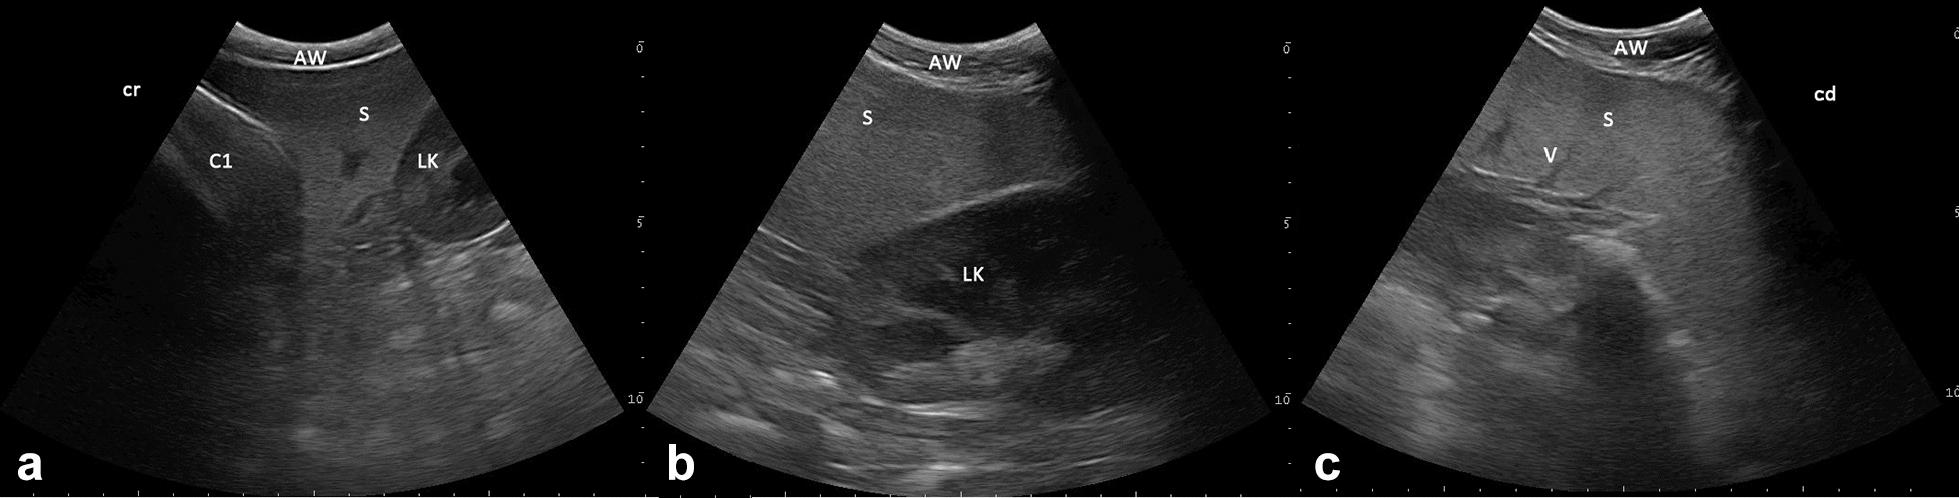

RESULTS

Ultrasonography was performed in 135 clinically healthy, non-sedated llamas and alpacas. Screening was performed with a 6.6 MHz curve linear transducer with only alcohol as contact medium between the probe and unclipped skin. The kidneys could be imaged from the paralumbar region. The right kidney only was visualized when scanning from the right and the left kidney only from the left. While the left kidney appeared in sagittal view as an oval shape in most llamas and alpacas, in one third of animals the left kidney had a triangular shape. The L-shaped base of the spleen, with its homogeneous, echoic pattern, could be seen craniolateral to the left kidney. Anechoic areas displaying vessels inside the spleen and a thin echoic capsule surrounding the splenic tissue could be differentiated. While sonographic appearances of the examined organs showed no differences between llamas and alpacas, selected dimensions of both of kidney and spleen showed significant differences between species. In terms of age and sex, significant differences in respect of kidney size could be found only in alpacas. Sex seemed to have no influence on kidney and spleen sizes in llamas.

本研究对 135 只临床健康、未镇静的羊驼进行了超声检查。使用 6.6MHz 线阵探头,仅以酒精作为探头和未修剪皮肤之间的接触介质进行筛查。可以从腰部旁区域对肾脏进行成像。从右侧和左侧仅能分别显示右侧和左侧的肾脏。虽然大多数羊驼的左肾在矢状视图上呈椭圆形,但三分之一的动物的左肾呈三角形。脾脏的 L 形基底,具有均匀的回声模式,可在左肾的颅侧看到。可以区分脾脏内显示血管的无回声区和围绕脾脏组织的薄回声包膜。虽然检查器官的超声表现没有显示出羊驼和羊驼之间的差异,但肾脏和脾脏的选定尺寸在种间存在显著差异。就年龄和性别而言,仅在羊驼中发现肾脏大小存在显著差异。性别似乎对羊驼的肾脏和脾脏大小没有影响。